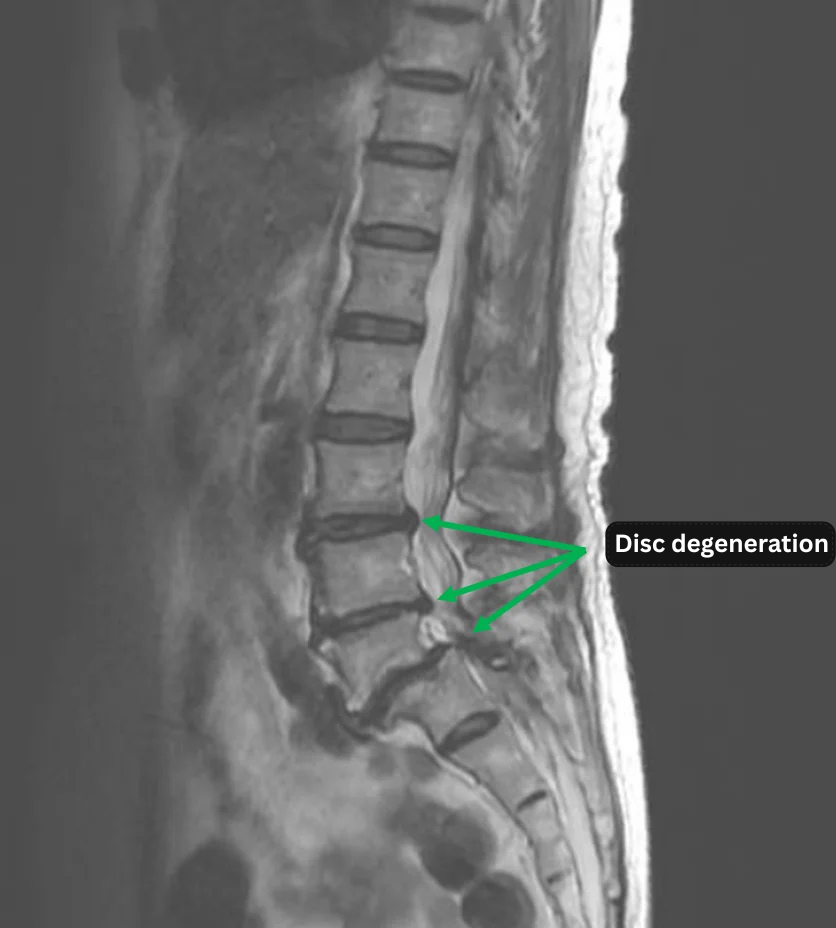

- L3/4, L4/5, L5/S: Disc degeneration

The above findings were also observed on the imaging.

・Disc degeneration at L3/L4 and L4/L5 is considered the most probable source of the symptoms.